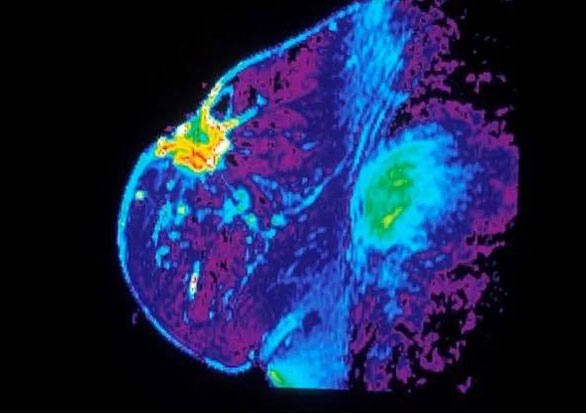

乳房MRI。圖源:Public Domain - National Cancer Institute

乳腺癌是全球女性最常見的癌種。根據(jù)美國癌癥協(xié)會的統(tǒng)計,美國一年內有超過25萬名女性被診斷出乳腺癌,4萬多名患者因乳腺癌去世。在中國,乳腺癌也是女性新發(fā)病例最多的癌種。